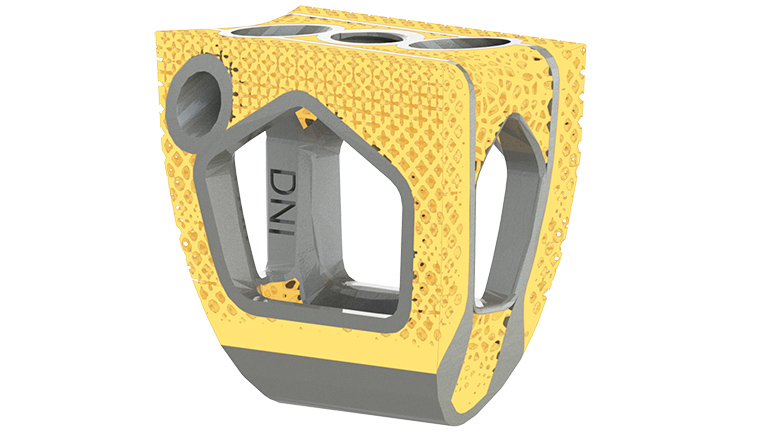

Supporting the full implant treatment process, Streamlining Additive Manufacturing For Spinal Implants,

Streamlining Additive Manufacturing For Spinal Implants, NexGen® Complete Knee Solution,

Improving off original VITA 46 standards, Amphenol's R-VPX, Evolution Spine New Product Launch – Ortho Spine News,